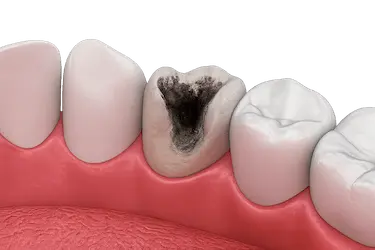

Las caries que avanzan hasta el interior del diente pueden llegar al nervio y causar una infección severa.

Con la endodoncia se elimina la pulpa dañada y se evita la extracción del diente.

Una vez que la pulpa del diente se ha lesionado, esta se inflama por el contacto con bacterias procedentes de caries o la propia saliva, infectando el interior del diente.

Si no se trata a tiempo, la infección se puede propagar hasta la punta de la raíz para formar un absceso, un granuloma (pequeñas protuberancias rojas que sangran fácilmente) o incluso un quiste.